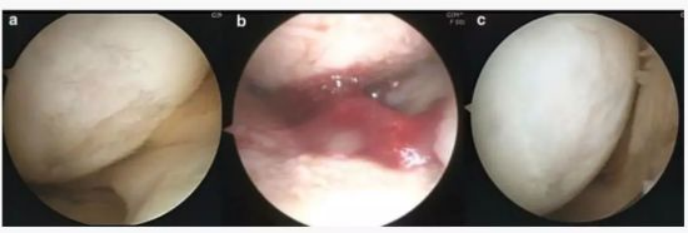

下图a为治疗前关节镜检查结果,,,可以看出软骨存在缺损。。图b为脂肪间充质干细胞联合PRP治疗,,,,图c为治疗后结果,,,通过间充质干细胞治疗,,,软骨得到了修复。。。

下图中A-C为51岁男性膝关节镜,,,D-F为54岁女性膝关节镜。。。A/D为治疗前,,白色示意软骨,,浅黄色示意裸露的骨。。。。B/E为间充质干细胞注射。。。C/F为治疗后的关节镜检查。。。。